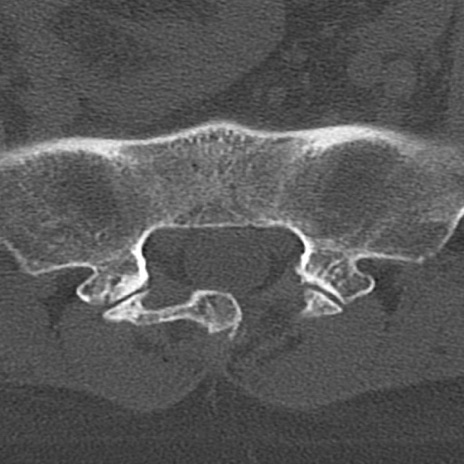

腰椎CT

冠状断像